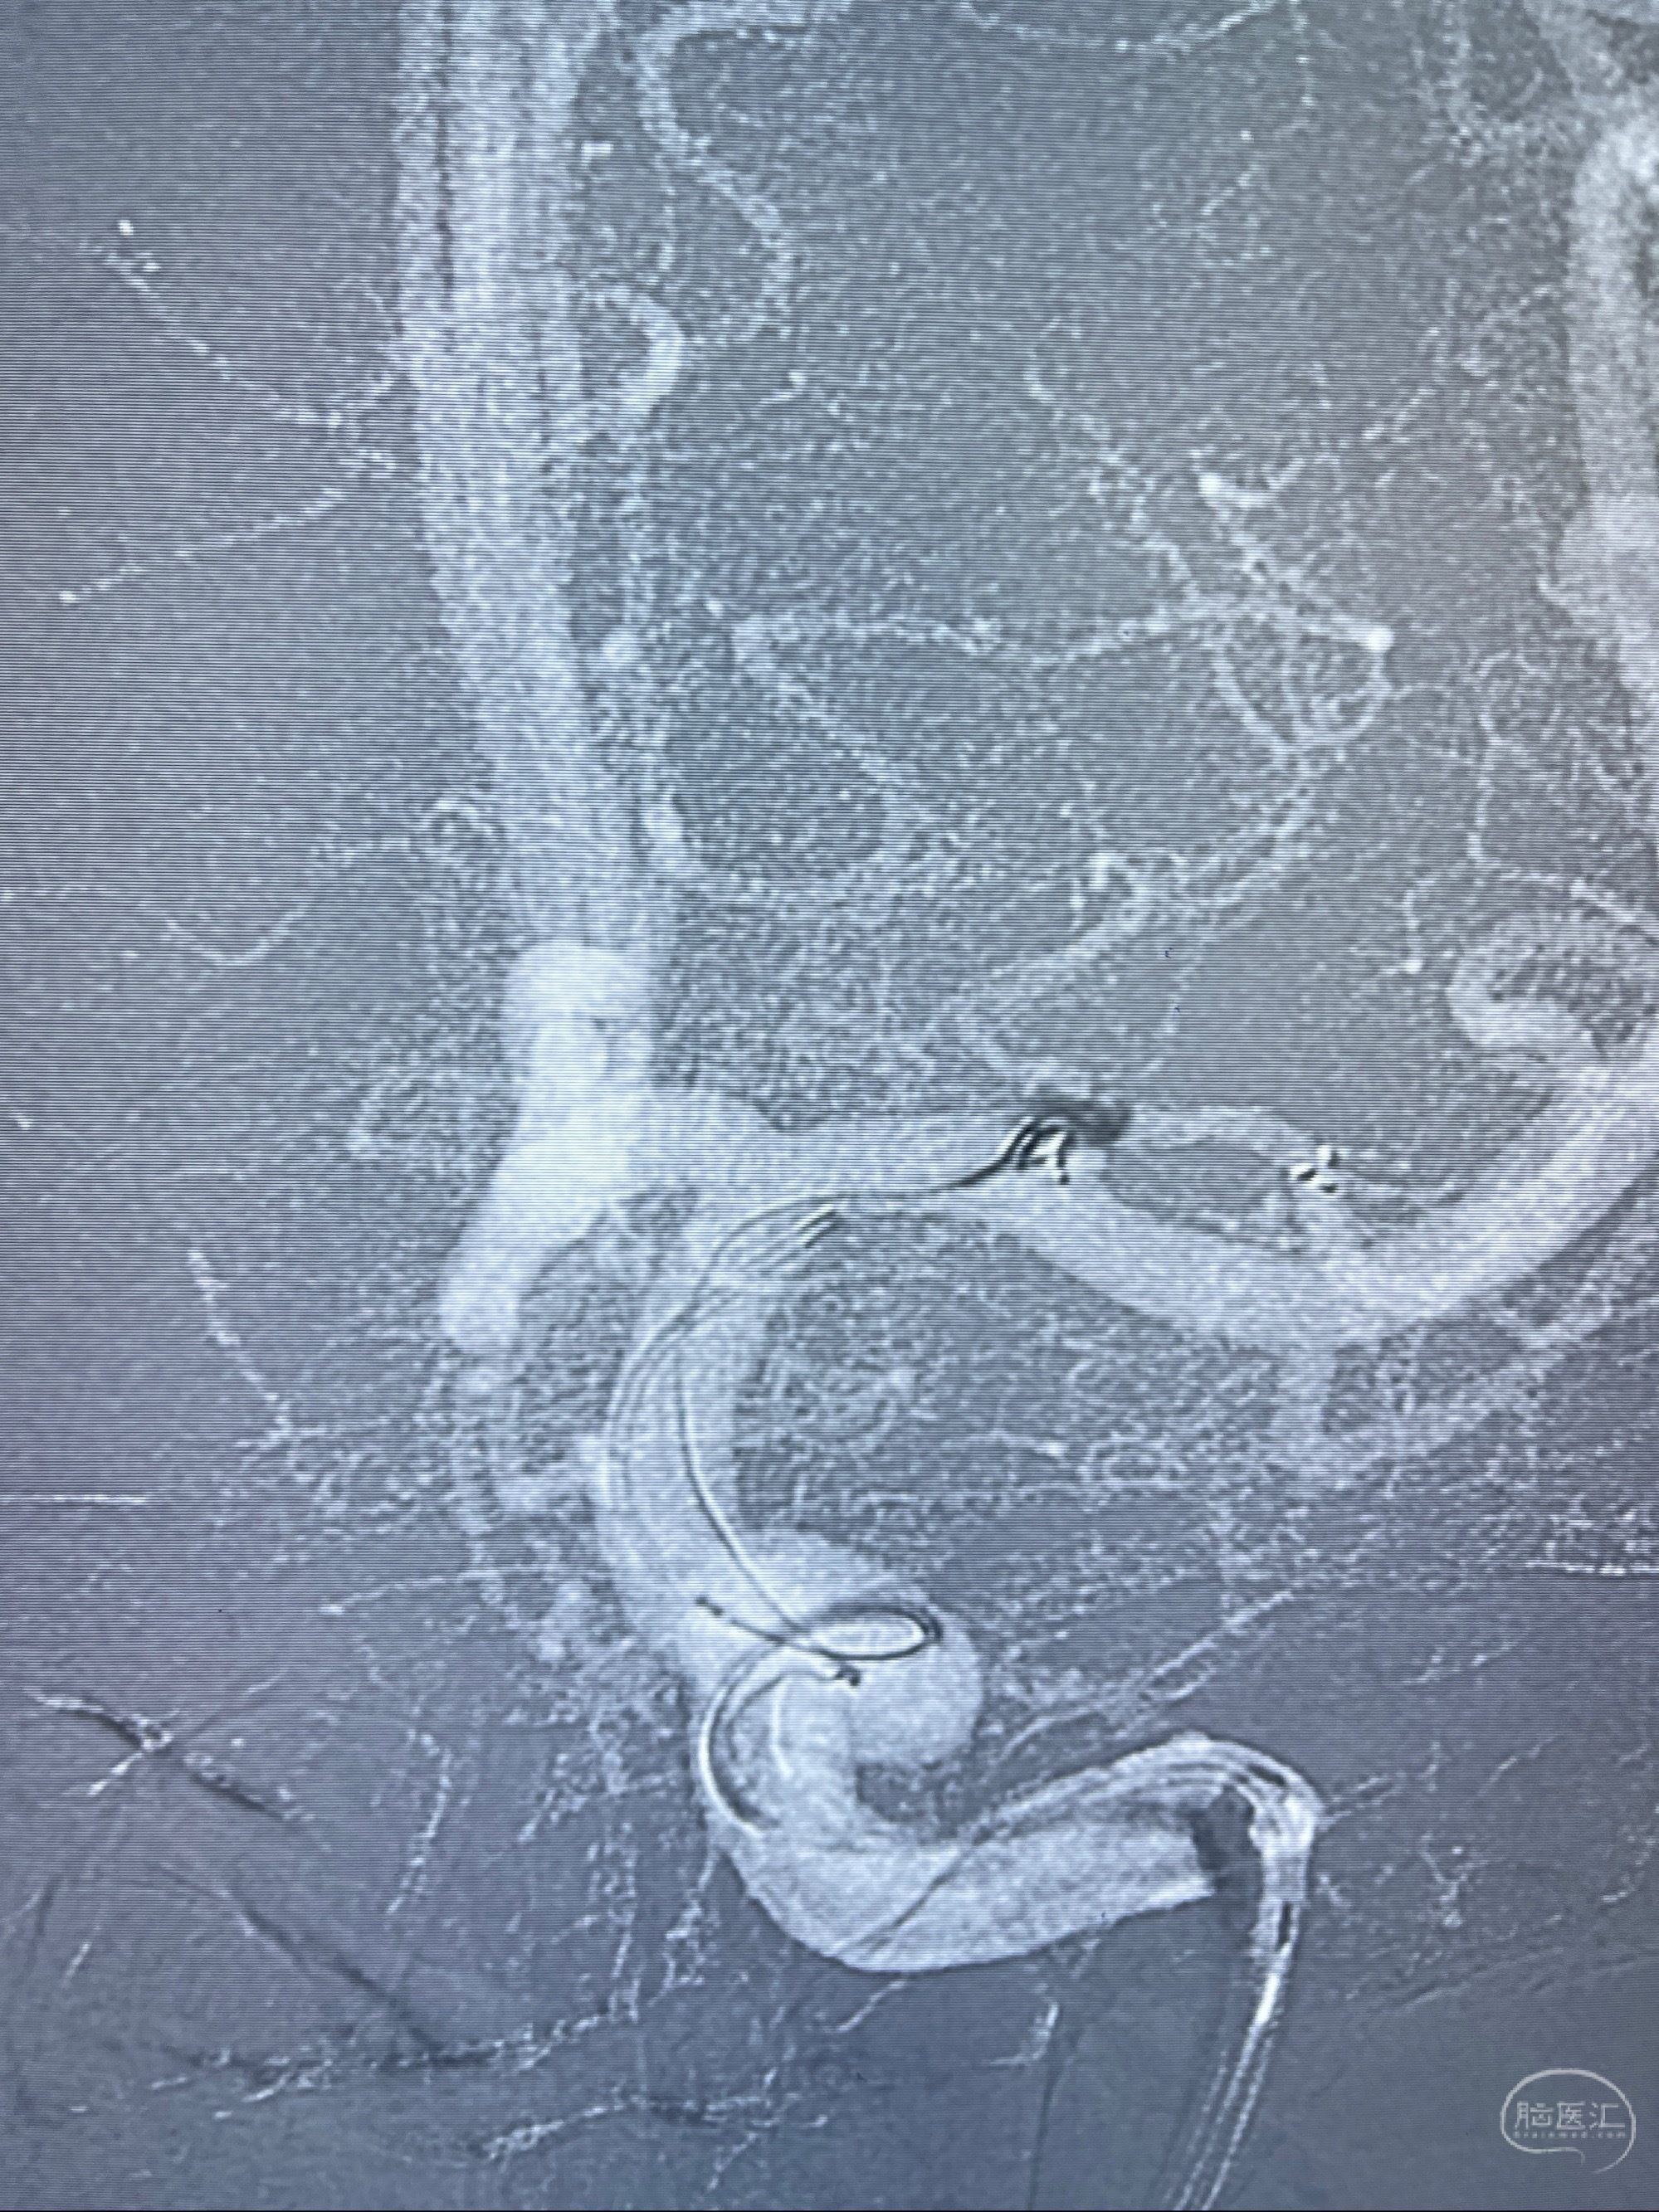

2023-08-14DSA:

左侧大脑中动脉动脉瘤,约2.6-2.8-3.4-2mm大小(瘤颈部、瘤体部、瘤高)

1.左侧大脑中动脉动脉瘤,约2.6-2.8-3.4-2mm大小(瘤颈部、瘤体部、瘤高)